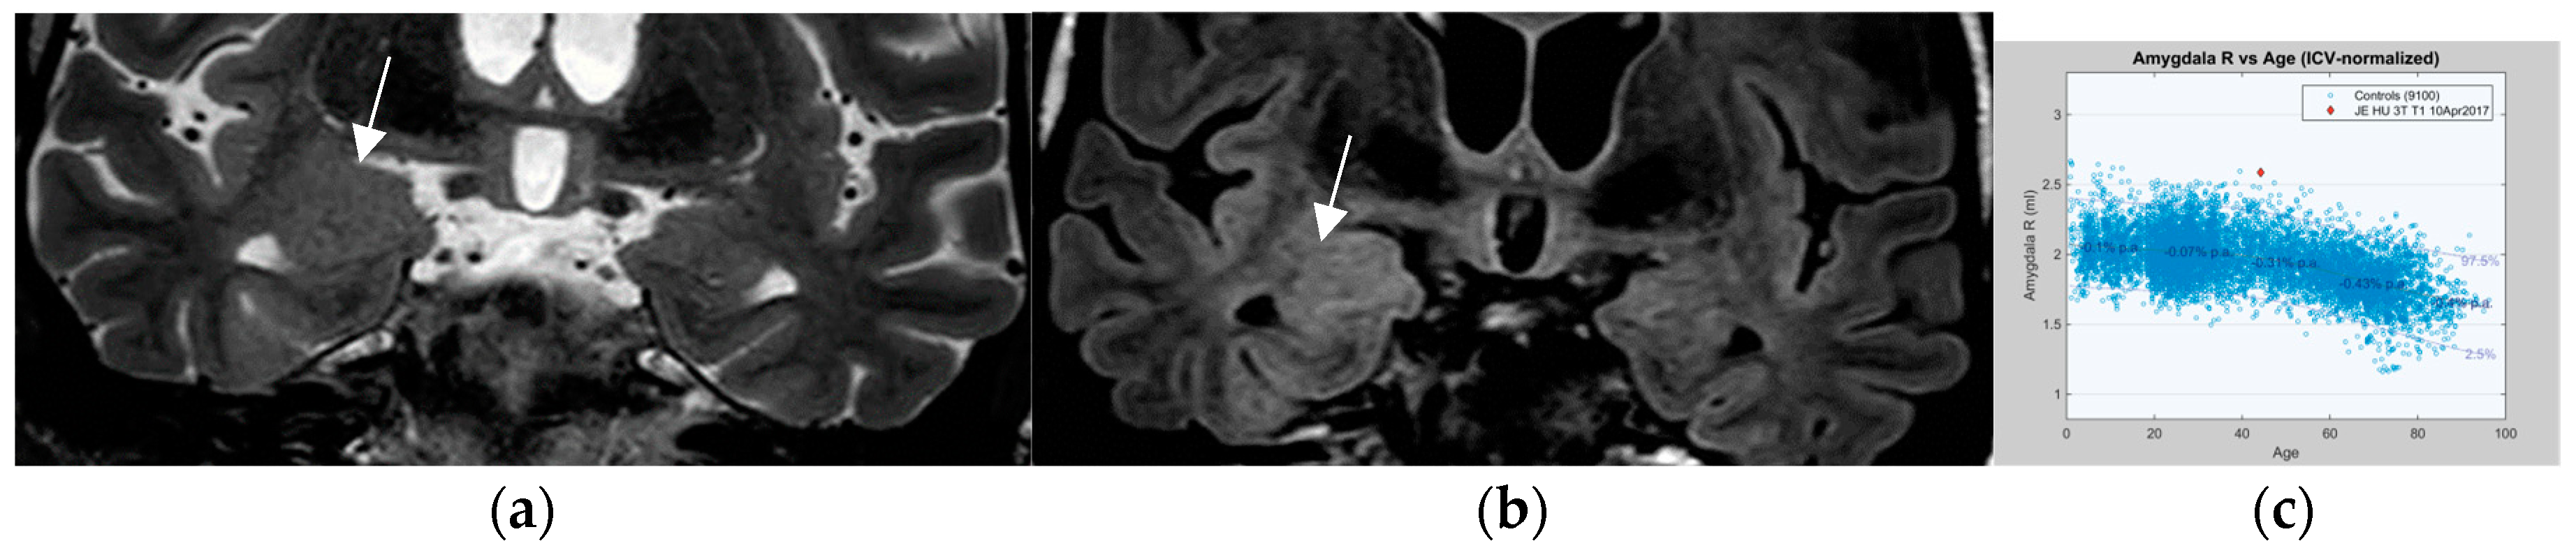

4.12. Contrast Administration Is of Limited Gain with Respect to Lesion Detection but May Contribute to Characterization of an Abnormality

Intravenous administration of Gd-based contrast agents in patients with epilepsy provides a low additional yield. In a study of 150 patients with focal epilepsy, contrast uptake was present in 33 out of 69 patients (47.8%) [88]. In fact, contrast enhancement only revealed two additional lesions (6.0%) that had passed unrecognized on nonenhanced sequences. The presence of contrast enhancement allowed for the characterization of lesions to better advantage and altered the diagnosis in 17 of 69 patients (24.6%). In patients who harbor a long-term epilepsy-associated tumour (LEAT) or patients with increased frequency of seizures, contrast administration may indicate a conversion of the dignity of a preexisting lesion (Figure 9) or a de novo abnormality.

Figure 9.

Left Precentral tuber on a sagittal FLAIR image ((a)—arrow) in a patient with known tuberous sclerosis. Recent-onset right focal motor seizures and transient speech arrest lead to a functional MRI. (a) Left speech dominance and precentral hand activation during motor task. New Gd contrast uptake is present on the axial MPRAGE Gd-enhanced sequence (b) in the periphery of the left precentral “active” tuber (arrow in (b)).

An additional entity that has increasingly attracted attention is nontumoral amygdala enlargement (Figure 11). Amygdala enlargement has been reported in 12% of patients with mesial temporal lobe epilepsy (MTLE) and was detected by volumetry and T2 relaxometry in patients without visible MRI abnormalities [91]. The etiology may be heterogenous: secondary and often reversible on MR in patients with adequate antiseizure medications response but may be termed “primary” based on amygdala dysplasia in those patients with an MR showing irreversible amygdala enlargement.

Figure 11.

Nontumoral right amygdala enlargement on a coronal T2 (1.7 mm arrow in (a)) and FLAIR sequence (0.9 mm) with signal elevation on the coronal FLAIR image (arrow in (b)) visually increased volume is confirmed to exceed 2nd standard deviation of normal value on volumetry (c).